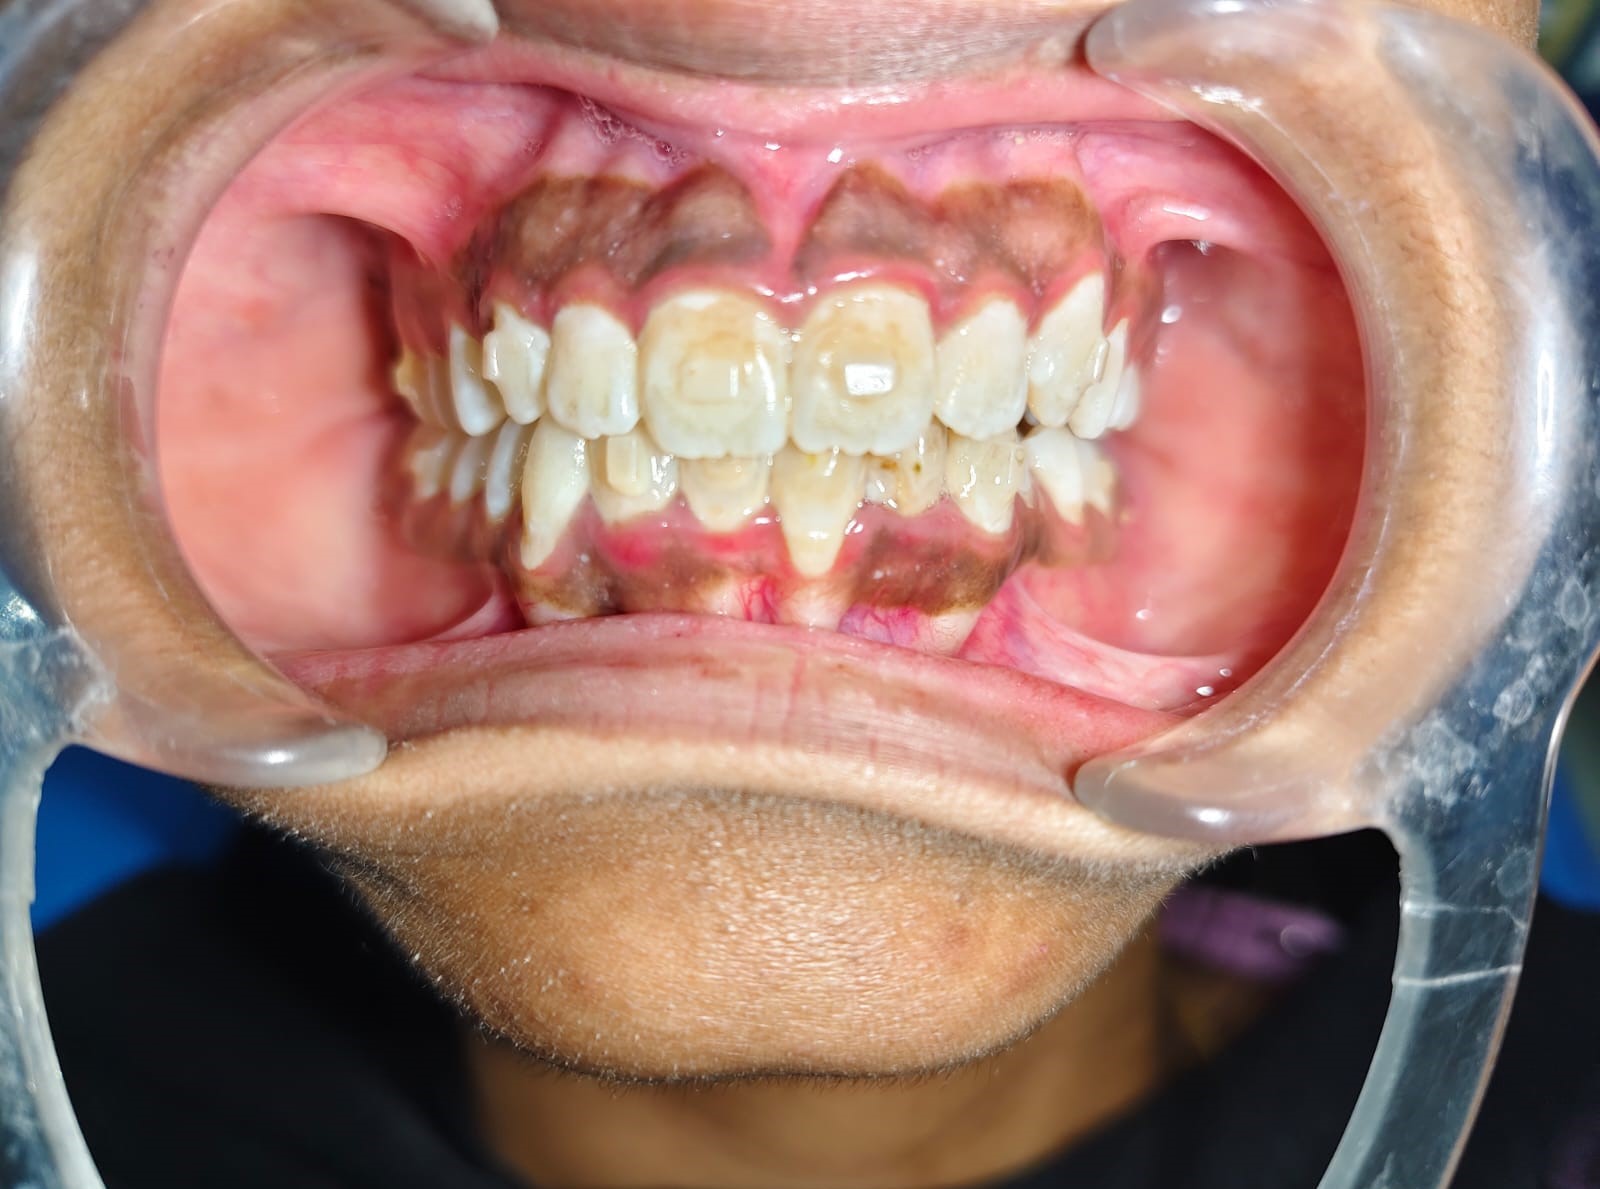

After/Before

See stunning smile transformation before and after

Before After